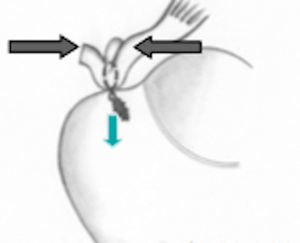

En la técnica de doble fila se colocan uno o dos anclajes mediales en el borde articular de la cabeza humeral, se pasan puntos sencillos a través del tendón y se anudan las dos suturas de cada anclaje con nudos deslizantes bloqueados. Los anclajes laterales se colocan en el borde lateral de la tuberosidad mayor y se anudan con las suturas mediales, ya sea con nudos deslizantes bloqueados o con los sistemas de no nudos existentes en el mercado. Una de las principales complicaciones en la reparación del manguito de los rotadores es la rerrotura, pero es muy importante tener en cuenta que en muchas ocasiones no existe una correlación directa entre una rerrotura, ya sea parcial o completa, con los resultados clínicos y funcionales44. Sin embargo, existe una relación directa entre la cicatrización y la fuerza postoperatoria (figs. 17–19).

Esquema de doble fila. Tomado de Ferry AT, Provencher MT, Yanke A, Verma NN, Bach BR, Romeo A. Double-row rotator cuff repairs: Biomechanical rationale and surgical techniques. En: Warren RF, Craig EV, eds. Techniques in shoulder and elbow surgery. Vol. 9. Philadelphia: Lippincott Williams & Wilkins; 2009. p. 2.